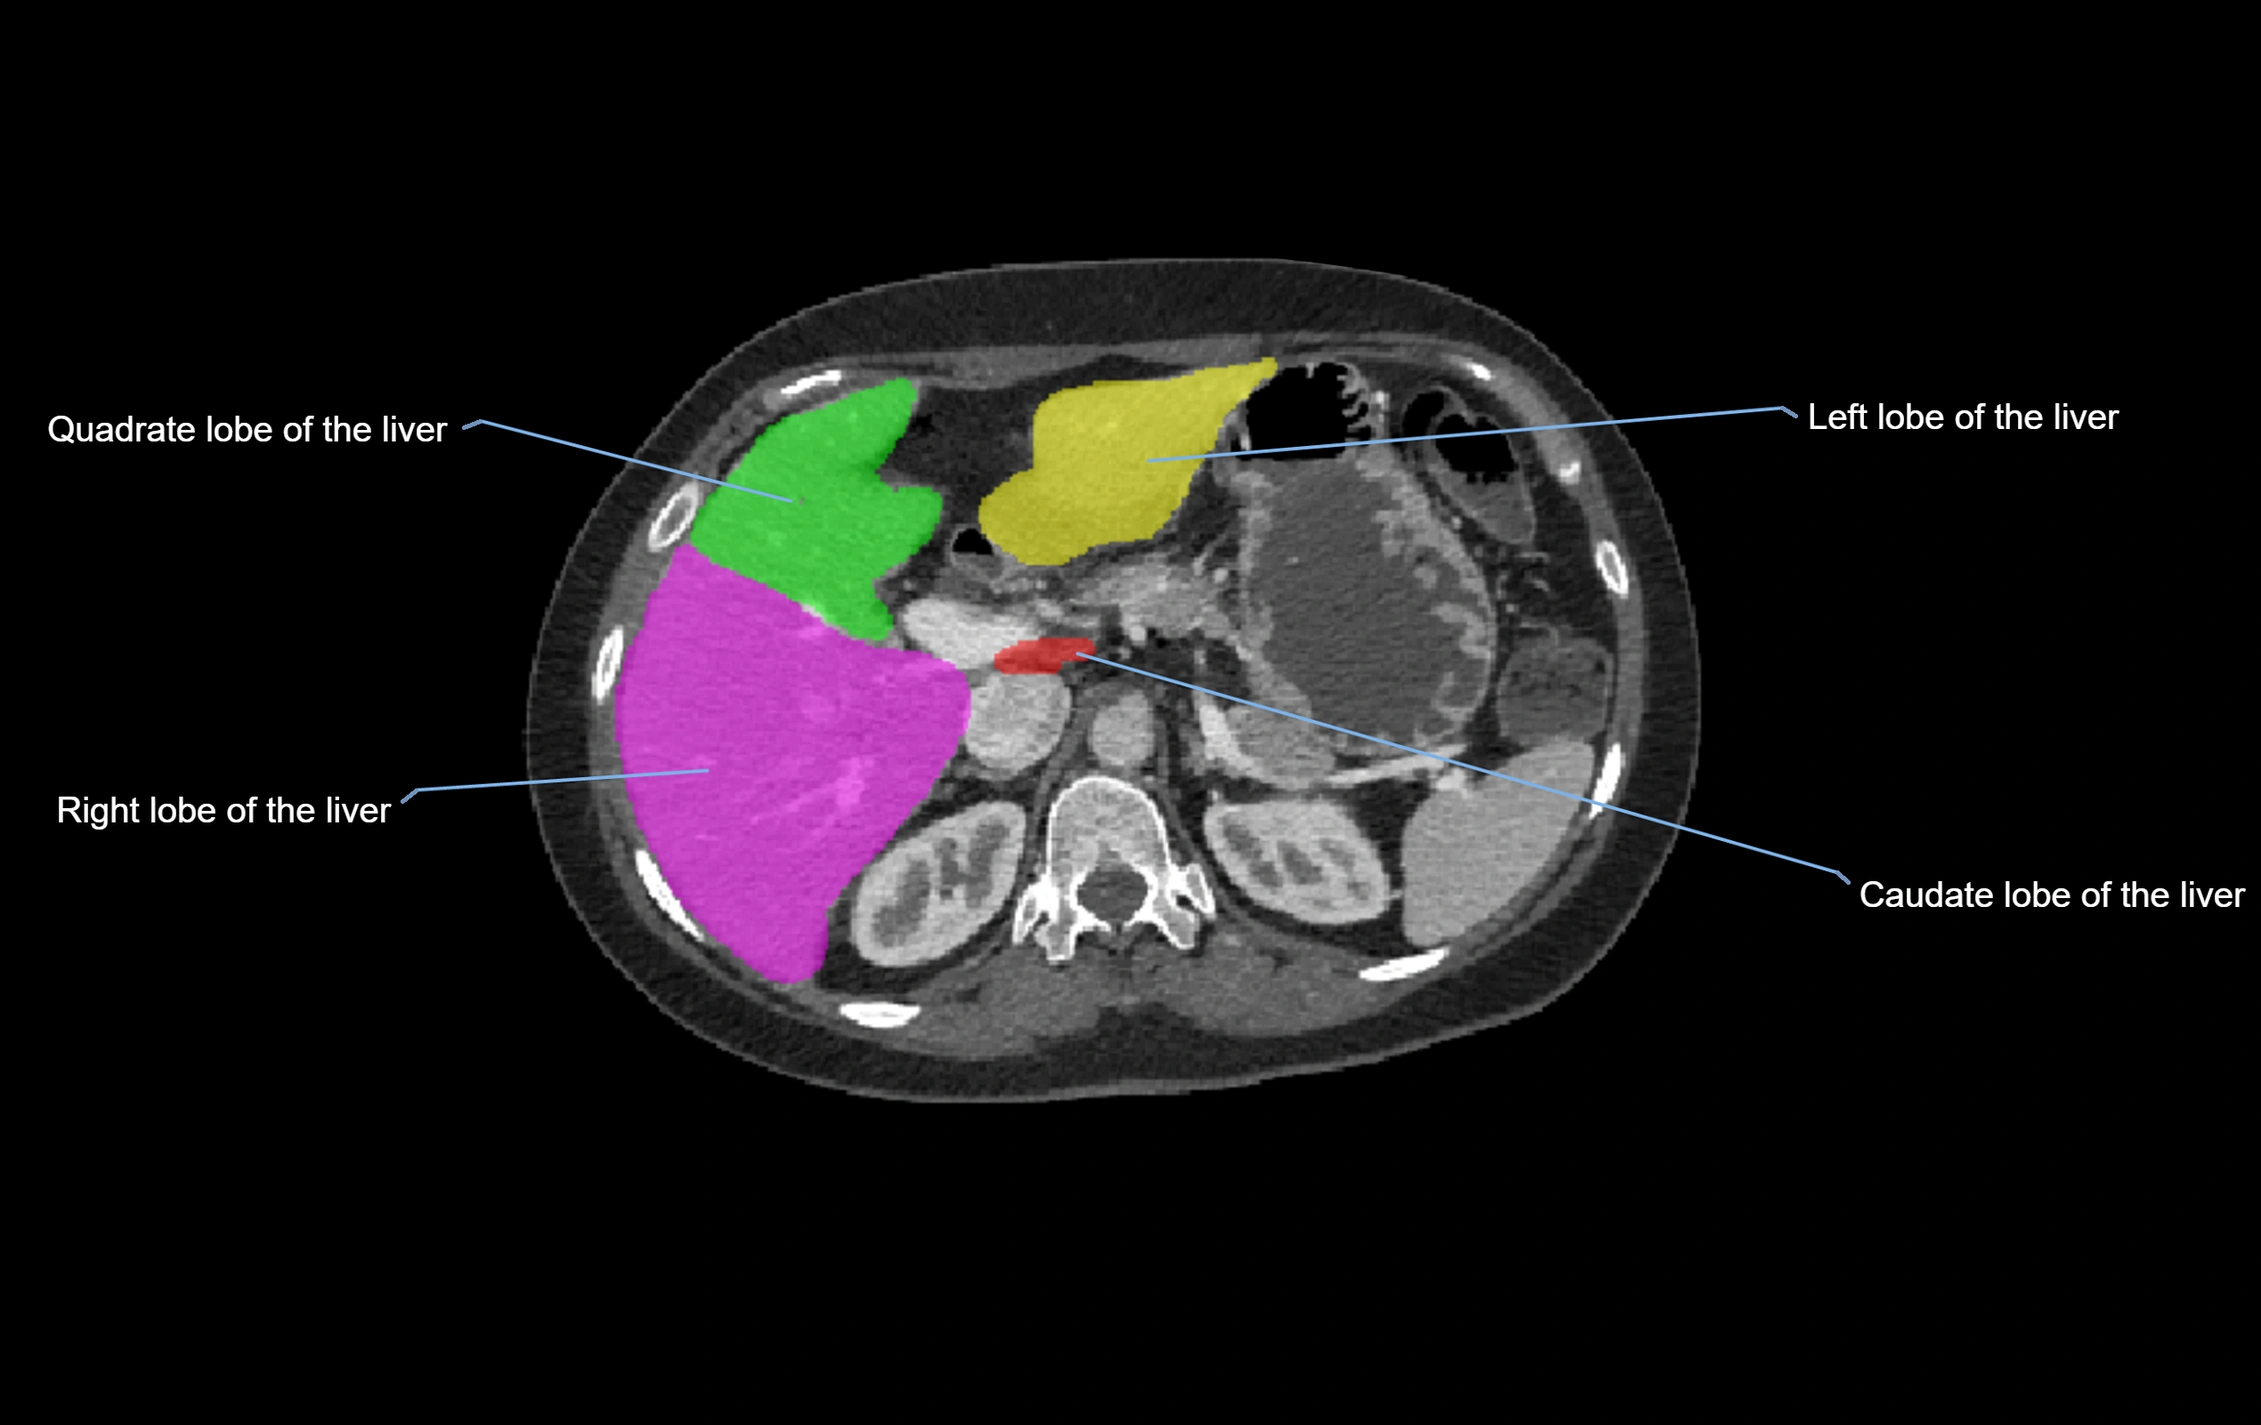

The caudate lobe of the liver is a distinct anatomical subdivision of the liver, designated as segment I in Couinaud’s classification. It lies on the posterior surface of the liver, between the fissure for the ligamentum venosum (left boundary) and the groove for the inferior vena cava (IVC) (right boundary). Superiorly, it is related to the posterior liver surface, and inferiorly it is separated from the left lobe by the porta hepatis.

CT Image

image